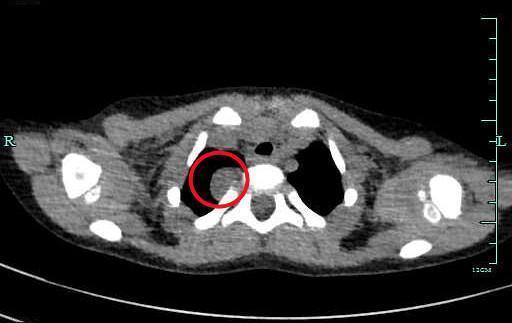

在儿童镇静中心的帮助下,乐乐顺利做了肺部CT,扫描结果清晰印证了肺部炎症的存在,放射科主任莫明华在阅片时,还敏锐地观察到乐乐CT图像上的异常:他的脊柱旁有一个大小约2.2*1.5cm的占位性病变。

占位性病变/医院供图

最终,乐乐确诊为“纵膈肿瘤”,经手术治疗后康复出院。